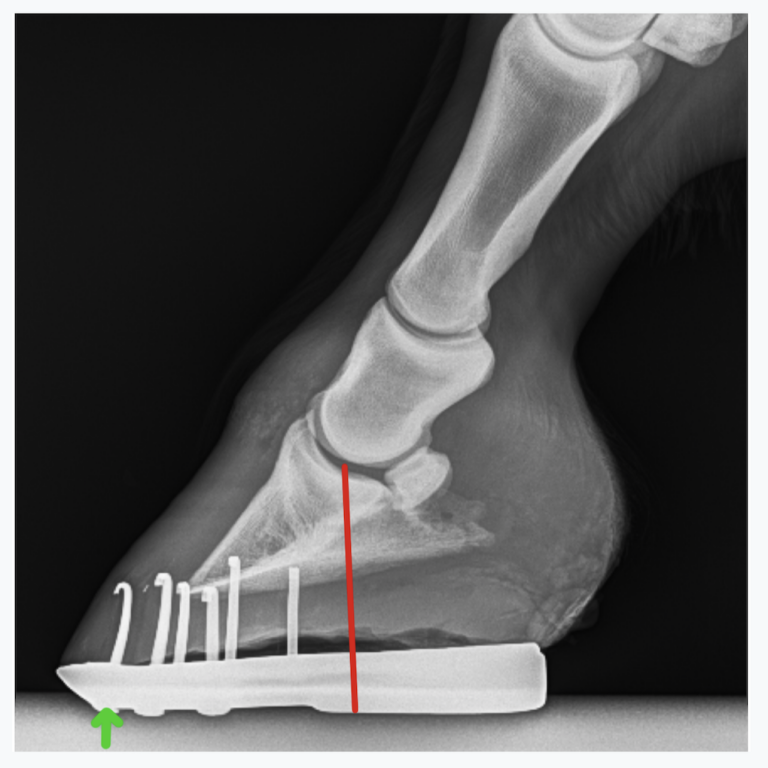

Do Horses With Navicular Need Shoes. Walter koepisch has seen his fair share of navicular horses. Shoes should relieve pressure on the navicular bone. corrective shoeing can help alleviate pressure on the navicular bone and support the horse's hoof structures. Farrier walter koepisch says there are a number of factors you need to consider when you’re shoeing a horse that has navicular problems. the equine digital support system is an effective shoeing method to achieve soundness. if your horse is diagnosed with navicular syndrome, your vet and farrier can devise a therapeutic shoeing plan. The sole is packed with impression material and a. one school of thought is that it is best to remove shoes to improve the blood flow to the feet, but others choose corrective shoeing, using a shoe that supports the heel and can reduce the load. shoe selection for horses with podotrochlosis also depends on discipline and disease severity, he adds. ideally, horses with navicular disease should never go barefoot. Shoes are not only helpful in addressing abnormalities and imbalances, they also. navicular shoe primer.